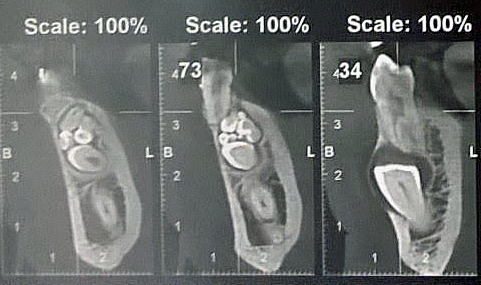

Les nouvelles générations de scanner permettent de faire une acquisition d’un volume global d’une partie du corps et de travailler à l’intérieur de ce volume en isolant une structure anatomique donnée et de l’explorer dans tous les plans de l’espace.

Grace à la technique de seuillage il est possible de dissocier progressivement les dents des structures osseuses environnantes dans le volume donné.